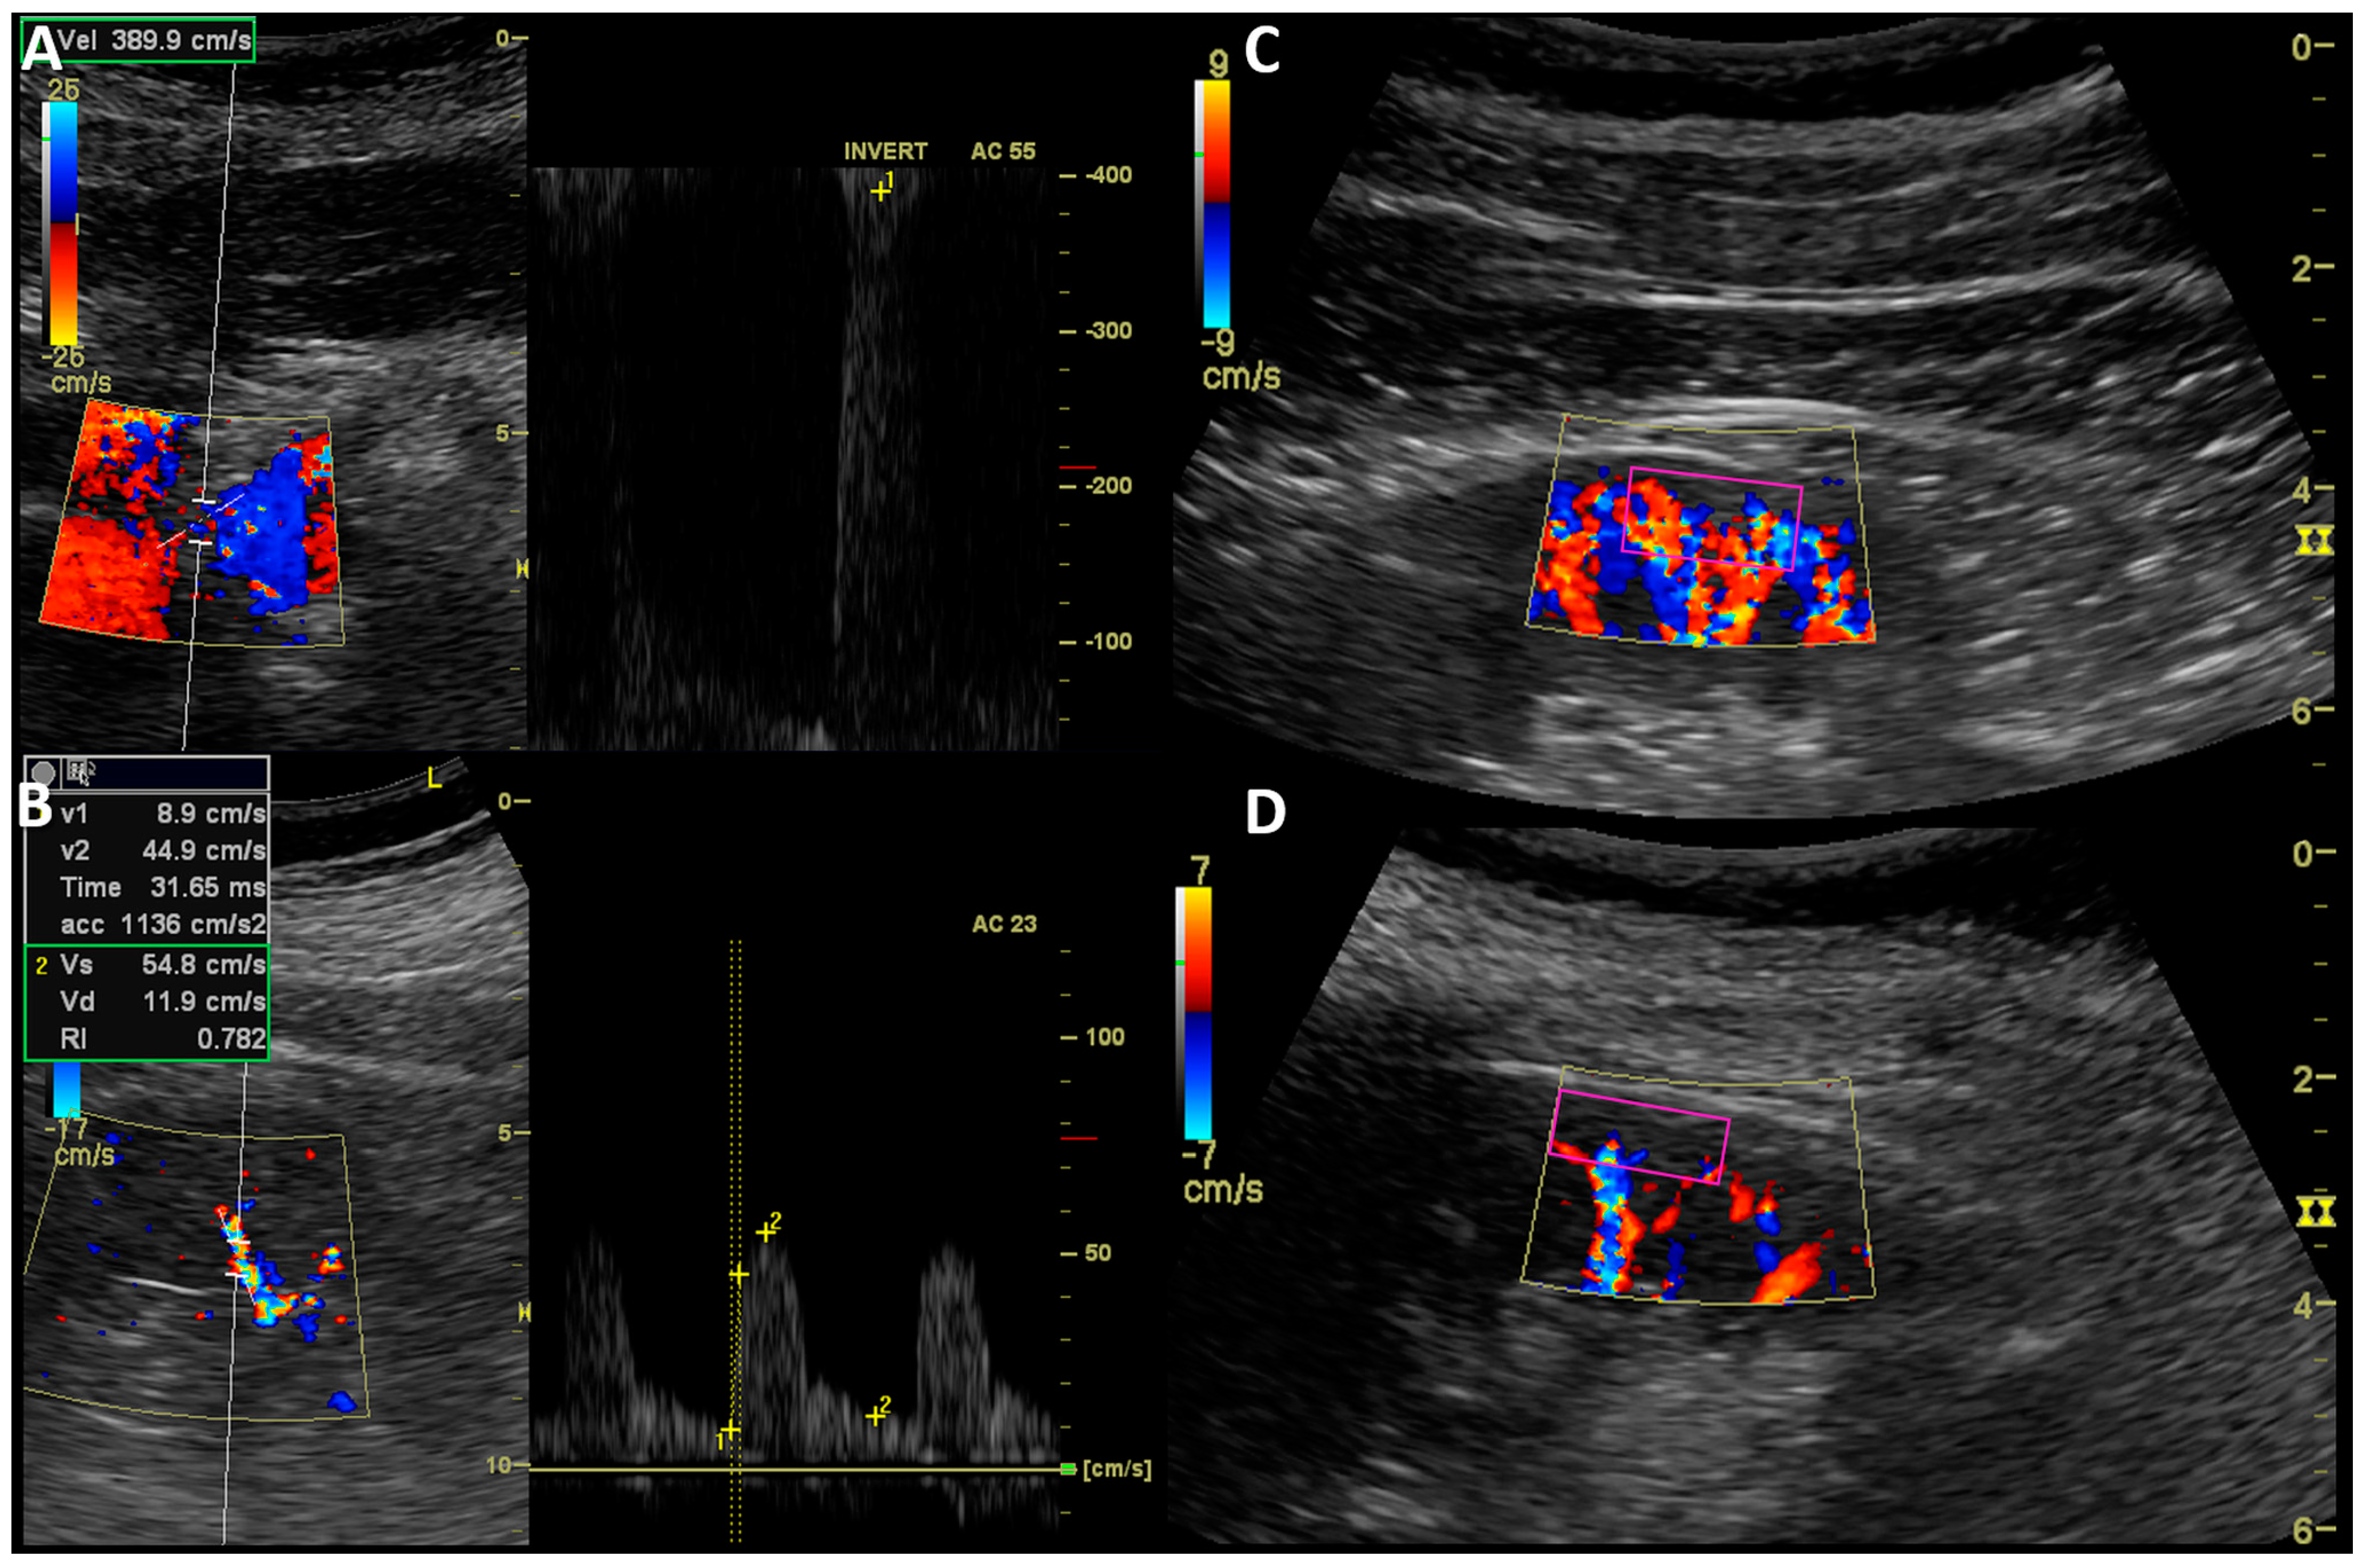

2.3. Kidney Ultrasound Assessment